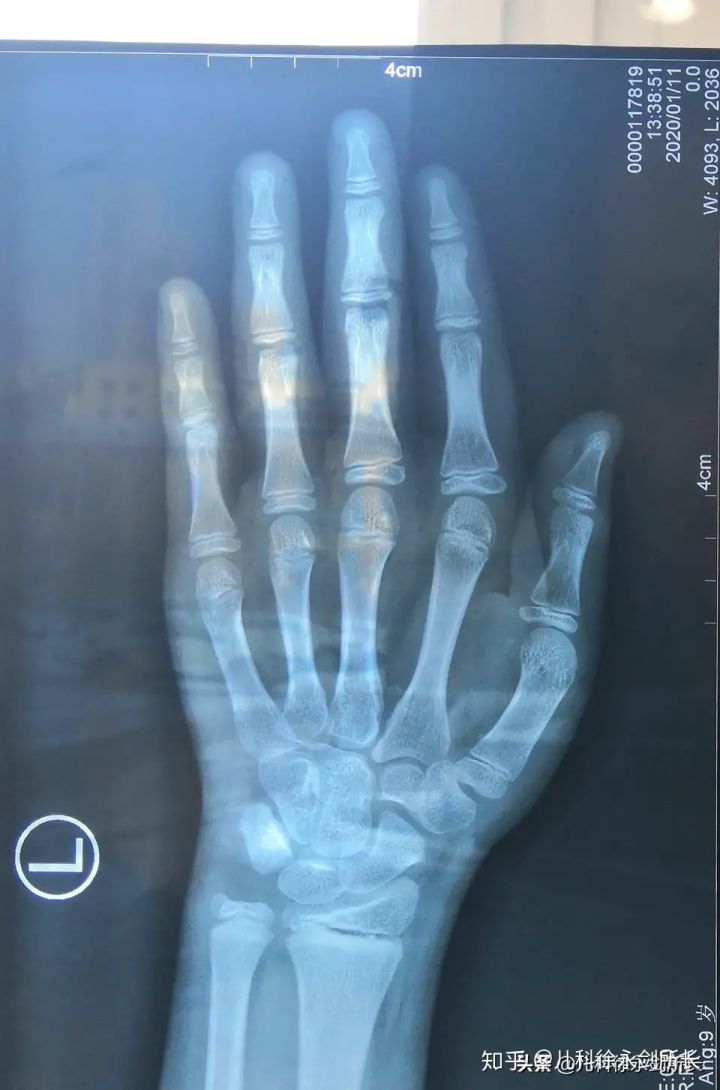

生长发育科徐永剑所长

13岁男孩的骨龄片子

软骨板呈现为一条线,好像将骨头的尾端断开了,这条线称为骨骺线